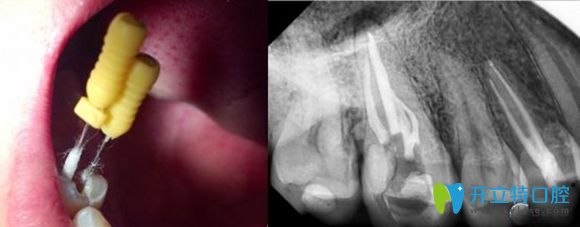

根管治療過程圖解

根管治療就是牙醫(yī)利用專用的器械,去除牙齒內(nèi)部感染的牙髓以及感染的牙本質(zhì),還有毒性分解產(chǎn)物,并進行適當?shù)南荆缓笤龠M行嚴密充填根管,防止發(fā)生根尖周病變,或者是促進根尖周病變愈合的一種治療方法。

牙齒根管治療科普圖

別看總結(jié)起來就一段話,實際上根管治療的程序可是非常復雜的,需要格外的細致。醫(yī)生操作起來既費時又費力,還不能一次診療即可完成,通常從初診到治療結(jié)束,需要3-4次的復診。

牙齒根管治療過程中圖片

根管治療后的X線片影像圖